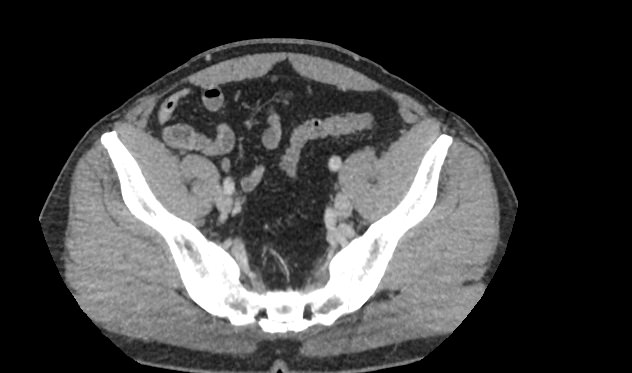

В брюшной полости и забрюшинном пространстве расположены группы лимфатических узлов, которые окружают внутренние органы (желудочные, печеночные, брыжеечные, чревные, подвздошные и др) и располагаются вдоль крупных кровеносных сосудов. Лимфоузлы относятся к периферическим органам иммунной системы человека и выполняют защитную функцию, являясь барьером для проникновения инфекций и задерживают распространение раковых клеток.

Патологические изменения регионарных лимфоузлов часто свидетельствуют о поражении того органа, от которого происходит лимфоотток. Это имеет важное значение для оценки распространенности онкологического процесса, выявления отдаленного метастатического поражения лимфатической системы, а также используется для определения тактики лечения. Кроме того, патология лимфатических узлов может говорить о развитии гемобластозов и лимфопролиферативных заболеваний крови.

Компьютерная томография позволяет детально визуализировать структуру лимфатических узлов, выявить ее неоднородность, гиперплазию, определить деформацию контуров, появление инфильтрации окружающих тканей с образованием пакетов и конгломератов лимфоузлов.

С целью повышения контрастности изображений, выявления патологических изменений в лимфоузлах дополнительно внутривенно вводится рентгеноконтрастное вещество на основе йода. Контраст накапливается в патологических очагах и под воздействием рентгеновских лучей обусловливает их яркое изображение на фоне неизмененной ткани. Контрастирование значительно повышает диагностическую ценность исследования и помогает выявлять многие серьезные заболевания на начальных этапах.

Что показывает КТ лимфоузлов с контрастом

• гиперплазия,

• неоднородность,

• пакеты, конгломераты лимфоузлов,

• изменения контуров,

• инфильтрация окружающих тканей,

• жировая ткань ворот узла,

• сдавление прилежащих органов, сосудов.

• уплотнение клетчатки, наличие жидкости.

• новообразование